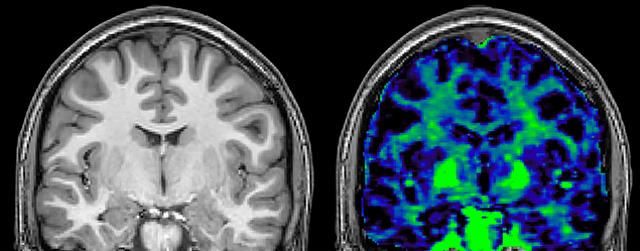

T1 - weighted

Myelin water imaging - T1 weighted

Myelin water imaging (echo 1)

Myelin water imaging with SENSE

Myelin water imaging with Compressed SENSE

With SENSE

With Compressed SENSE

Acquired resolution:

1 x 2 x 5 mm3

1.5 x 2 x 3 mm3

Number of echoes:

32 or 48

56

Echo spacing:

10 ms or 8 ms

7 ms

T1 - Weighted, Myelin Water Fraction Superimposed

MWI Spinal cord coverage

Spinal cord coverage

MWI Smaller, more isotropic voxels

Smaller, more isotropic voxels

MWI Excellent detail in quantitative maps

Excellent detail in quantitative maps

Images courtesy of Adam Dvorak, Department of Physics and Astronomy, University of British Columbia

20%

Myelin water fraction

0%